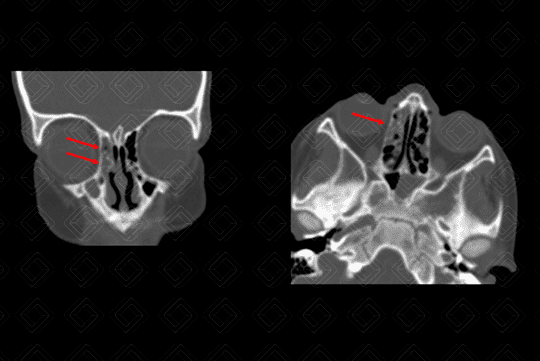

Texto alternativo para a imagem Figura 2. Créditos: Dra Elazir Mota - Rio de Janeiro/RJ

Descrição da lesão: Tomografia computadorizada de seios da face com cortes axiais, seguida de reconstruções coronais. Preenchimento completo do seio maxilar direito (seta branca na figura 1) e parcial das células etmoidais bilateralmente (setas vermelhas na figura 2), associado à obliteração do infundíbulo deste lado. Observa-se, ainda, espessamento mucoso concêntrico do seio esfenoidal esquerdo (asterisco na figura 3).